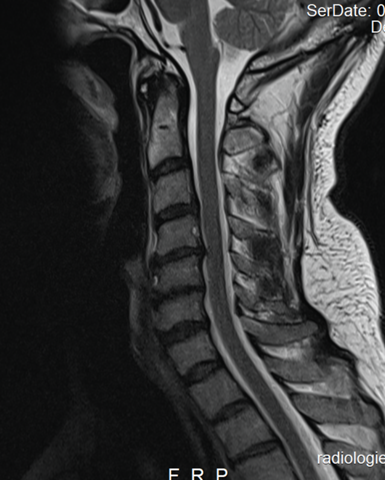

Tauche Arme und Beine 10 Minuten lang oder bis das Kribbeln verschwunden ist in ein Kaltwasserbad. Kribbeln in den Händen Unterarmen werden häufig mit einem Bandscheibenvorfall im HWS Bereich assoziiert. Spürst du öfter ein Kribbeln in der Hand.

Diese Art von Missempfindung hat meist direkte und harmlose Ursachen wie eine falsche Liegeposition oder Kälte. Ursachen können bei den Armnerven oder bei der Halswirbelsäule liegen. Kribbeln in Armen Fingern Händen Eingeschlafener Körperteil.

Ursachen können bei den Armnerven oder bei der Halswirbelsäule liegen. Zur besseren Wirkung kannst Du den gesamten Körper mit ätherischen Ölen einreiben. Ursachen können bei den Armnerven oder bei der Halswirbelsäule liegen. Kribbeln ist eine Empfindungsstörung Parästhesie auf der Hautoberfläche die von überaktiven sensiblen Nerven herrührt. Warum das so ist und was du sofort dagegen tun kannst verraten wir dir in diesem Artikel. Kribbeln durch den Mausarm RSI-Syndrom Auch ein Mausarm RSI-Syndrom kann Kribbeln und Schmerzen auslösen. Kribbeln in den Armen ist ein Fall für den Neurologen. Meistens geht das Kribbeln mit einem Taubheitsgefühl einher die Gliedmaßen fühlen sich an wie eingeschlafen. Hier durch entsteht das Kribbeln aber nicht sonde.